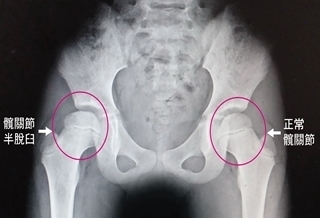

走路像鴨子 竟是髖關節脫臼

走路像鴨子 竟是髖關節脫臼#脫臼

(優活健康網記者徐平/綜合報導)一名初學滑直排輪的8歲女童,屢屢摔倒,一直感覺右邊腹股溝疼痛,後來走路出現一跛一跛情況,就醫後經X光檢查發現,該女童的右側髖關節半脫臼,醫師提醒,髖關節半脫臼如未妥善治療,有可能會導致脊椎側彎或走路外八字的嚴重後果。假性長短腳 右腳有些微較短澄清醫院中港院區復健科主治醫師董莉貞表示,經髖關節外展理學檢查發現女學童的右側腹股溝部位有疼痛現象,而兩腳已出現假性長短腳,右腳有些微較短,強烈懷疑是髖關節的問題。做X光檢查,證實是右側髖關節半脫臼,從影像可以看出她的股骨頭有部分跑出髖臼之外,才造成腹股溝疼痛及假性長短腳現象,由於病情並不嚴重,建議立即進行復健治療。徒手進行髖關節展延並加強臀肌力量復健治療部主任蔡永裕指出,由於該女童的髖關節半脫臼導致關節活動角度受限,是一跛一跛走進復健治療部,經短波治療儀增加關節的延展性,再徒手進行髖關節展延運動並加強臀肌力量,讓半脫臼的髖關節即早恢復到原來的活動度,經持續2週復健治療,該女童已恢復正常走路姿態。臀部橫向皺痕不對稱 即早求醫孩童罹患髖關節半脫臼並不容易,除了先天性外,有可能因經常性的撞擊所造成,如果未接受妥善的復健治療,可能會導致脊椎側彎、跛行,董莉貞醫師強調,至於先天性的髖關節半脫臼,家長要細心觀察,如發現小孩兩側臀部橫向皺痕不對稱、長短腳、走起路來外八字像鴨子走路一樣,就要即早求醫,接受最適當的治療。